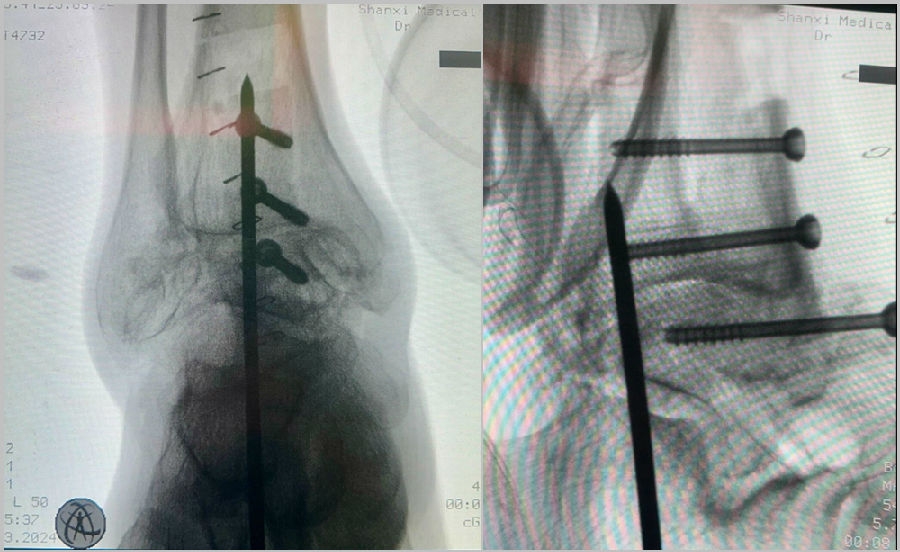

固定方法:

病例报告之二,xx,男,56岁,左踝创伤性关节炎。左踝崴伤6年,疼痛加剧3年。切口显露同前。

手术前资料

手术中资料

23 手术后资料